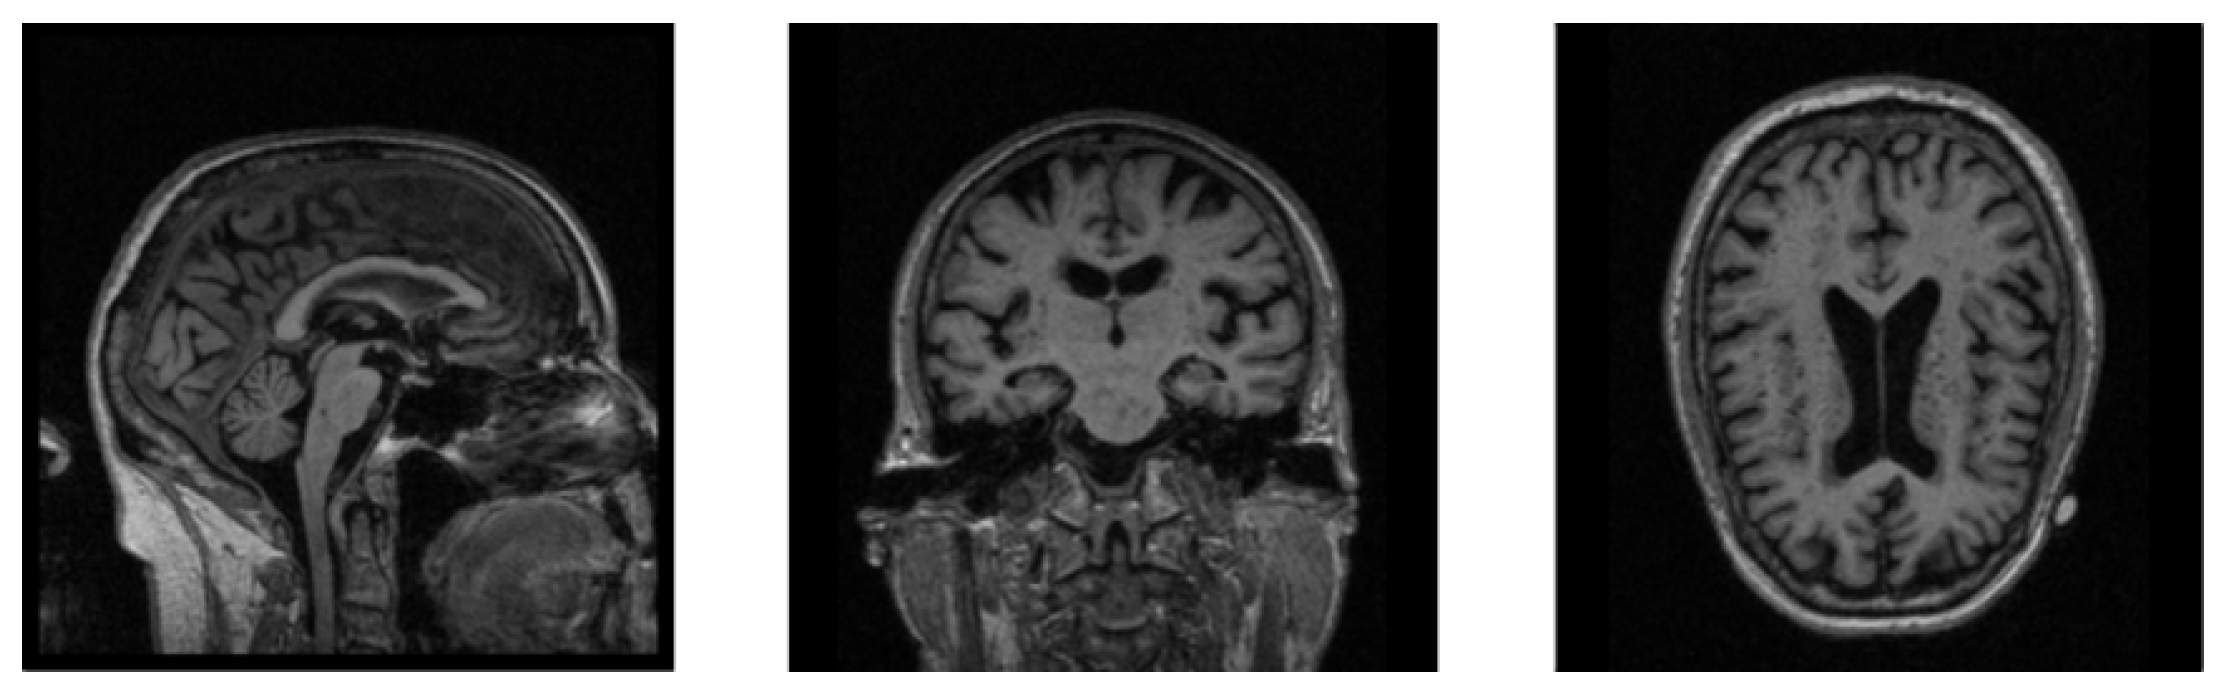

The MRI images are mostly 3D data, which contain more information than 2D data while requiring a larger amount of calculation during training, which makes neural networks less efficient when training 3D MRI data. In Figure 2, we show the sectional views of a 3D MRI image along three directions (sagittal plane, coronal plane, and axial plane). We can clearly see that there are many black noise regions near the margins of each image. These regions contain a lot of useless boundary voxels, which have no impact on brain tissues and need to be processed prior to training the neural network. The introduction of a large amount of noise not only slows down the process of model training, but also reduces the accuracy of diagnosis. The motivation of the data denoising module is to provide more valuable data for AD diagnosis as the inputs of our neural network, so as to improve the diagnostic accuracy of our network model. Based on this, a data denoising method is proposed, which removes the marginal noise regions in raw data to accelerate network training and improve diagnostic accuracy.

Figure 2.

The sectional views of a 3D MRI image along three directions. The three views from left to right are sagittal, coronal, and axial.